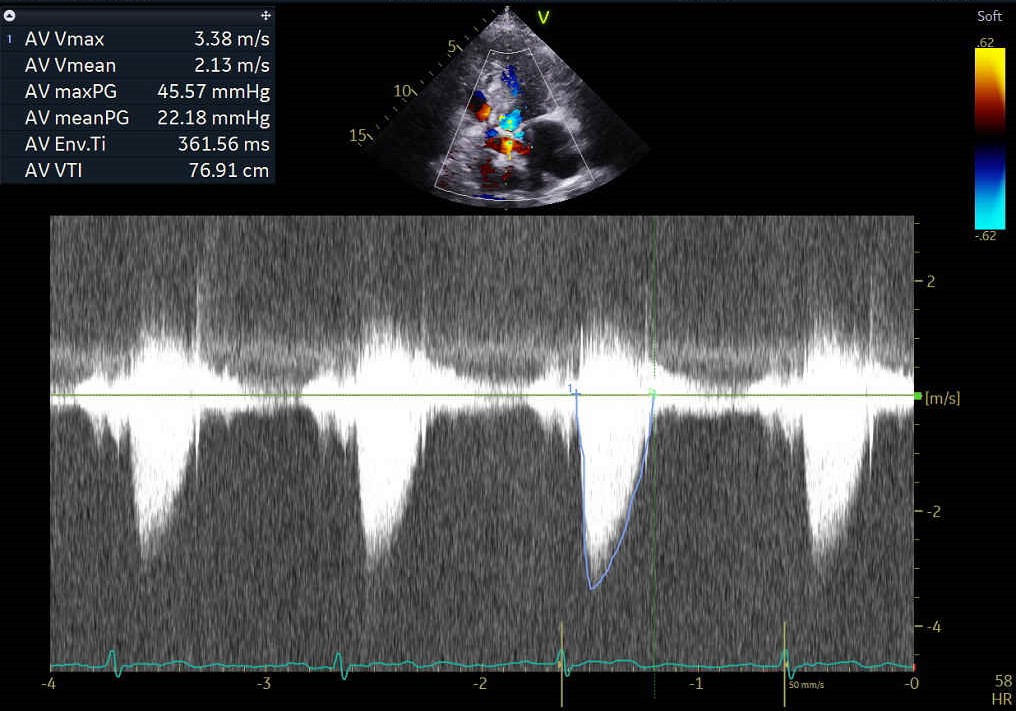

The echocardiographic findings indicate an LVEF of 55%, an aortic valve area of 0.77 cm², a maximum velocity of 3.28 m/s, a mean pressure gradient of 22 mmHg. Intermittent shortness of breath and heart failure symptoms have been reported for more than six months and are deemed to be related to low flow, low gradient severe aortic stenosis. His surgical risk, represented by an STS score of 12.4%, reinforces the decision to proceed with the TAVI intervention.